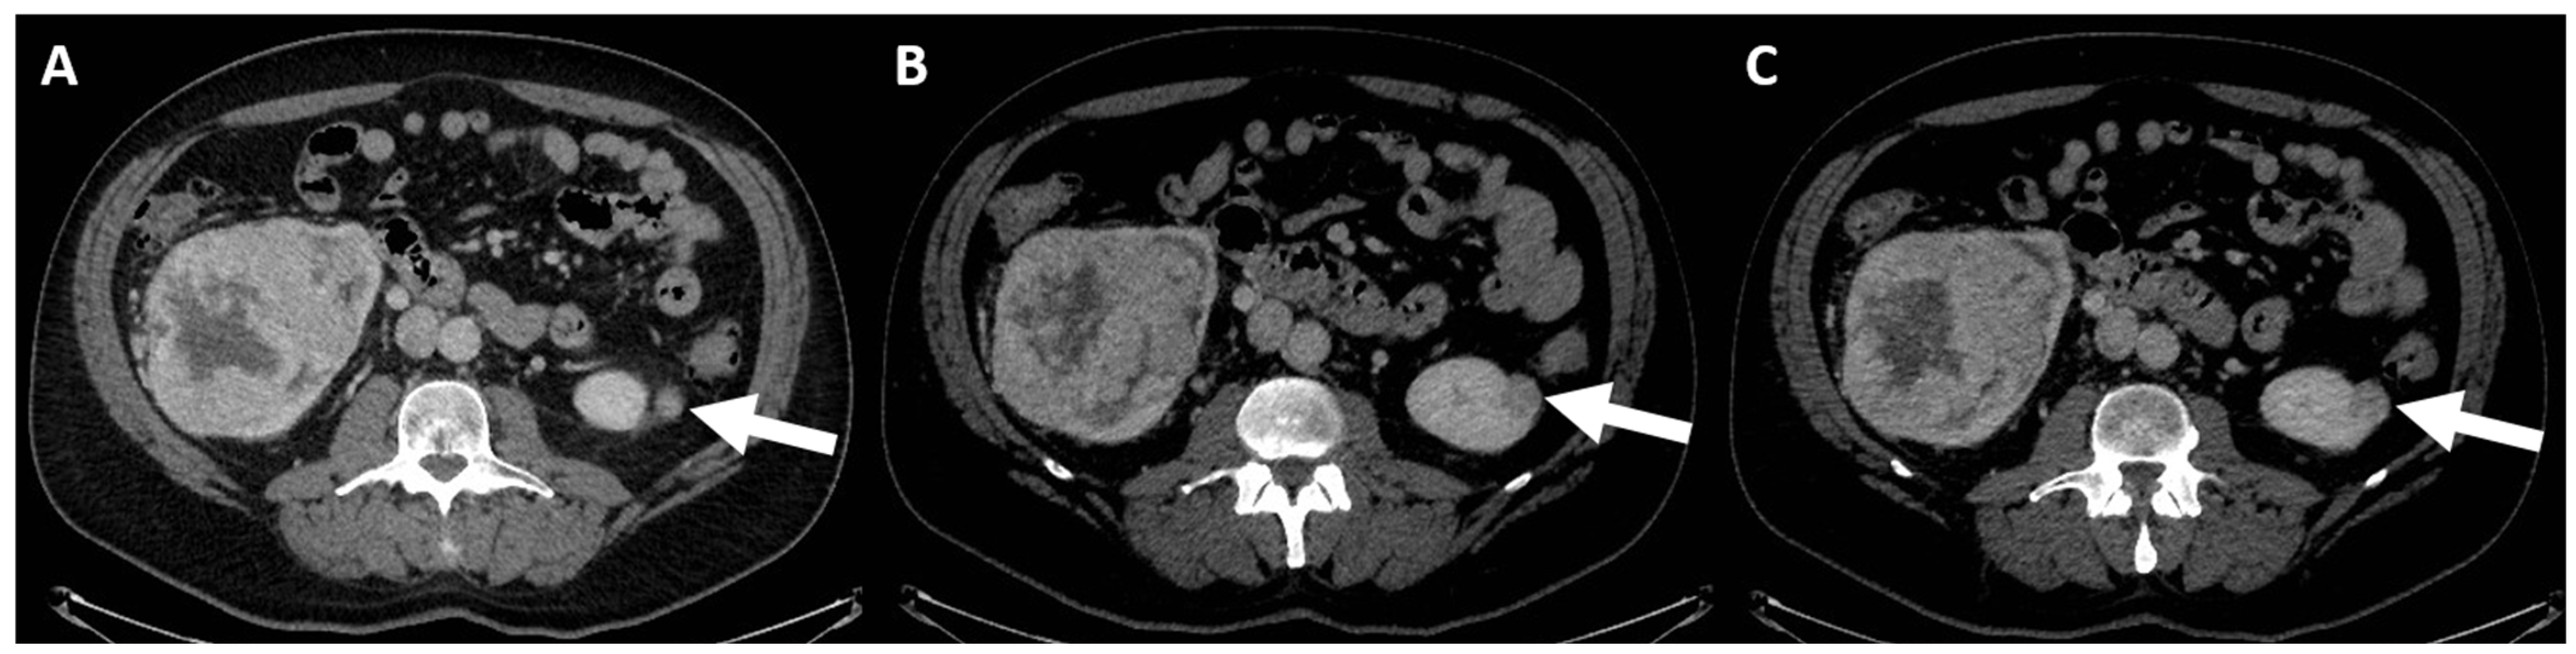

5. Cystic Renal Masses and Bosniak Classification

- (d) Class III: indeterminate cystic mass, which includes cystic masses characterized by one or more thickened (≥4 mm) or enhancing and irregular (≤3 mm and with convex marginal protrusions) walls or septa [91]. Bosniak III masses (Figure 4) are “potentially” malignant in that they have an intermediate probability of malignancy (about 55%) [97]. Therefore, urologic consultation should be considered for possible partial nephrectomy or radiofrequency ablation in candidates unfit for surgery [99].

- (e) Class IV: clearly malignant cystic mass, which includes masses characterized by the presence of one or more enhancing nodules (≥4 mm convex protrusion with obtuse margins, or a convex protrusion of any size that has acute margins). A Bosniak IV mass (Figure 5) has a malignancy rate of about 90% and therefore requires urologic consultation to perform partial or total nephrectomy [100].